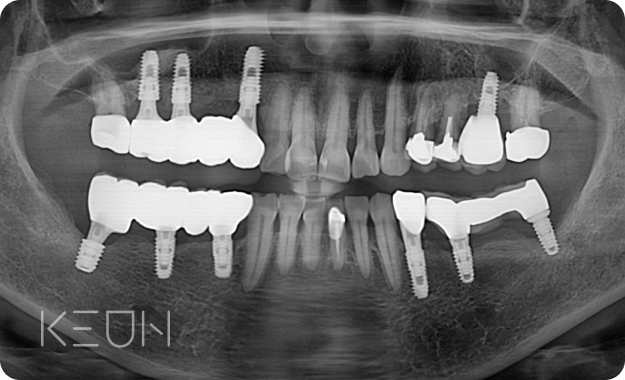

임플란트 재치료.

임플란트는 대중화되어 제 3의 치아라는 명칭을 얻고 있지만,

보철물의 수명, 시술 중 발생하는 문제, 사후관리 미흡 등으로 재치료를 받는 경우가 많습니다.

- Before

- After